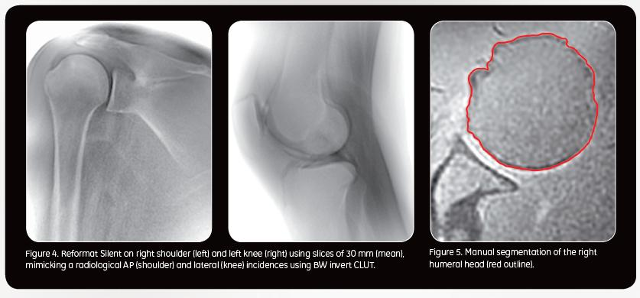

Los médicos del hospital madrileño, que está reconocido por la FIFA como centro médico de excelencia, serán de los primeros de Europa en utilizar una innovadora tecnología de RM de 1,5T denominada Signa Voyager*, una de cuyas principales características es su capacidad para poder suministrar imágenes de alta calidad del hueso cortical, es decir de la capa exterior del hueso, algo que, hasta ahora solo estaba al alcance del TAC o de la radiografía convencional.

El uso de la resonancia magnética en este tipo de lesiones en partes duras del cuerpo humano podrá ampliar de manera sustancial la capacidad diagnóstica en problemas óseos y permitir poder diagnosticar de manera precoz patologías degenerativas como la artrosis, la osteoporosis y los problemas de cartílago, así como planificar intervenciones quirúrgicas.

Tal como destaca el Dr. Mario Padrón, jefe del Servicio de Radiodiagnóstico de la Clínica CEMTRO, "la gran ventaja de esta nueva tecnología que estamos validando en la clínica es que permitirá poder ver y diferenciar claramente en una sola prueba las partes duras y la estructura periférica de los huesos, es decir, las partes blandas que lo rodean como músculos, tendones, grasa y tejidos fibrosos". Según el Dr. Padrón, "esto puede que evite en muchos casos, tener que exponer al paciente a una segunda prueba como el TAC, que es preferible no realizar si no es estrictamente necesario, sobre todo en niños y en pacientes que han de someterse a muchas pruebas".